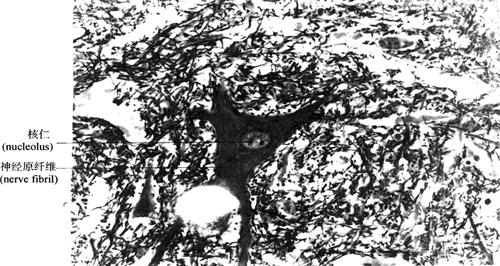

(1)胞体:神经元胞体是细胞的营养中心,细胞核位于胞体中央,大而圆,染色浅,核仁明显。胞质称核周质(perikaryon),含有发达的粗面内质网、游离核糖体、高尔基复合体和微丝、微管、神经丝等。在光镜下,粗面内质网和游离核糖体呈嗜碱性颗粒或块状,称为尼氏体(Nissl bodies)(图2-45),主要功能是合成蛋白质(包括合成神经递质有关的蛋白质和酶)。直径约为10nm的神经丝(neurofilament)常集合成束,在胞体内交织成网,伸入突起内则平行排列,在银染切片中呈棕黑色细丝,称为神经原纤维(图2-46),对神经元起支持、传递信息和运输等作用。某些神经元胞体含有分泌颗粒,内含激素,具有内分泌功能,称为分泌神经元(secretory neuron)。

图2-46 脊髓前角运动神经元镀银染色(示神经原纤维)(400×)